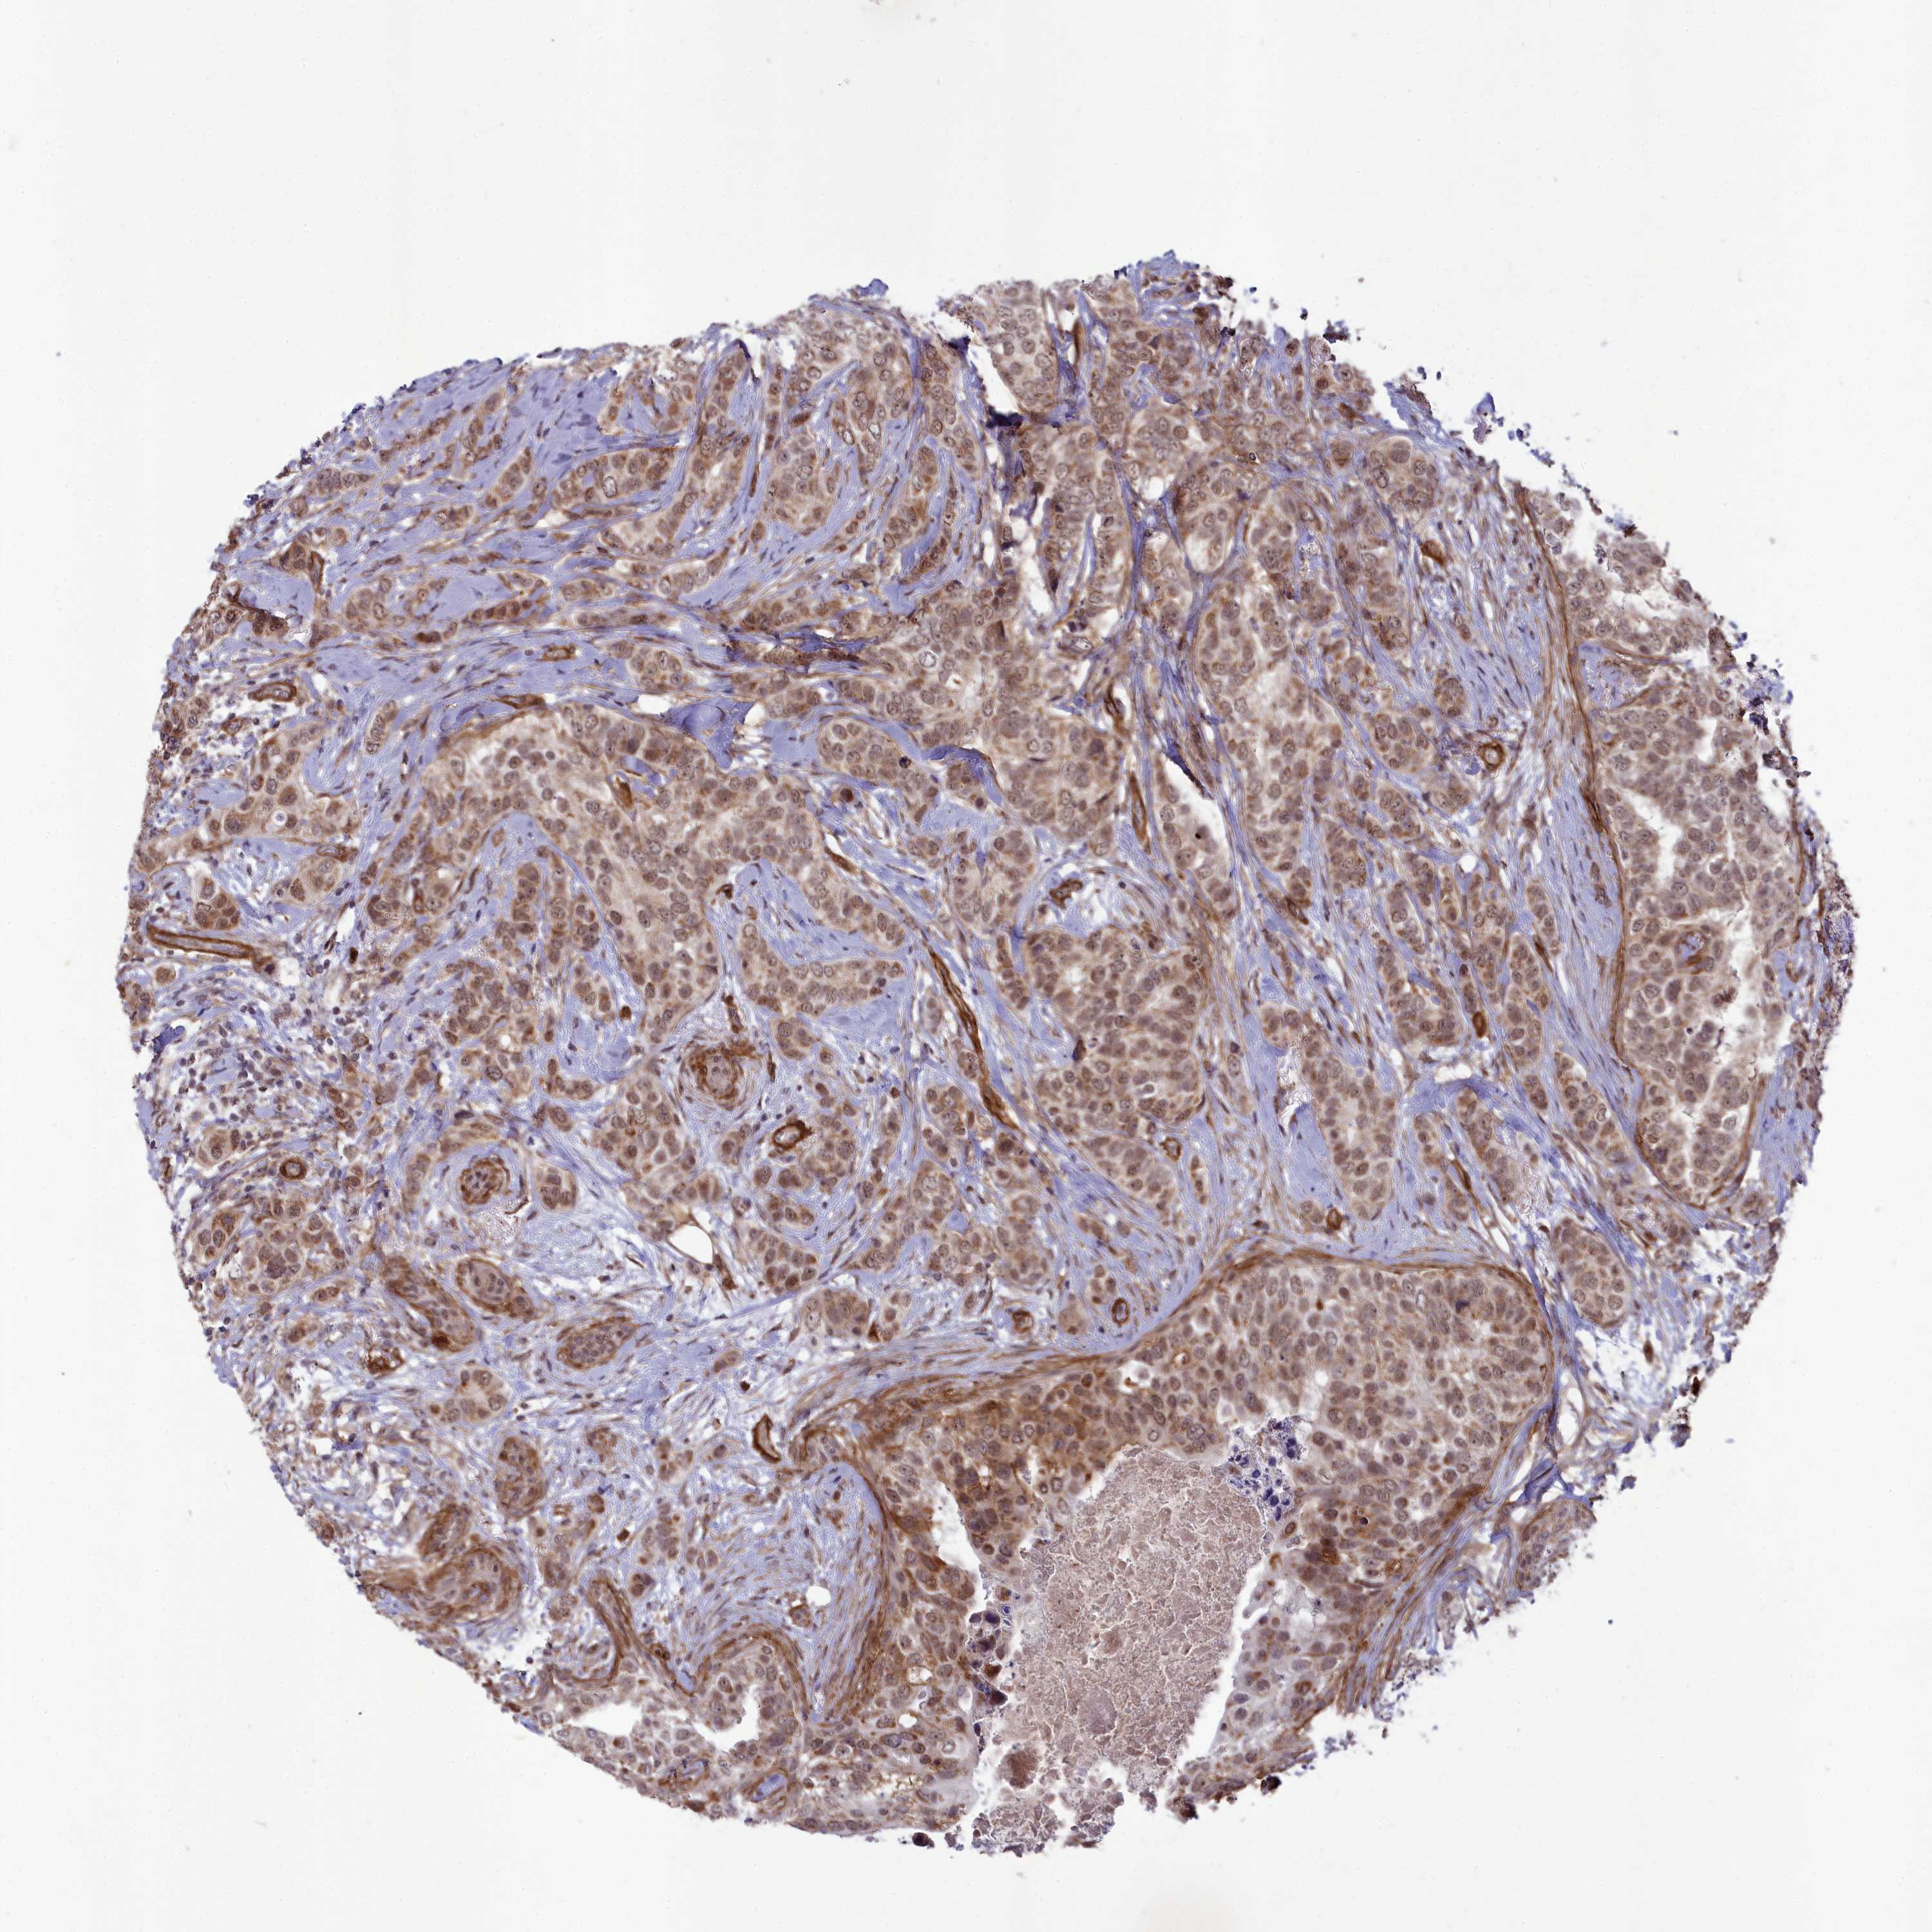

CANCER BREAST CANCER Show tissue menu

BRCA TCGA BRCA VALIDATION PROTEIN EXPRESSION